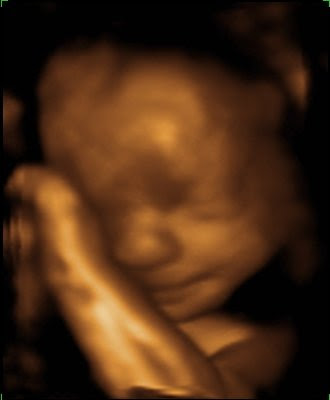

28 Weeks.

Today I got to see LB! He’s beautiful (to me) and I’m smitten even more. He seems to have an abundance of personality.

He smiles. (He frowns too.)

He’s peaceful. (He’s grouchy too.)

He sucks his thumb. I hope this means he’ll take to the breast.

He looks like he’s a sweetie-pie.

He poses. (And puts up with the paparazzi.)

I’m so in love. I can’t wait to meet him face to face.

What a wonder technology is. Truly amazing.